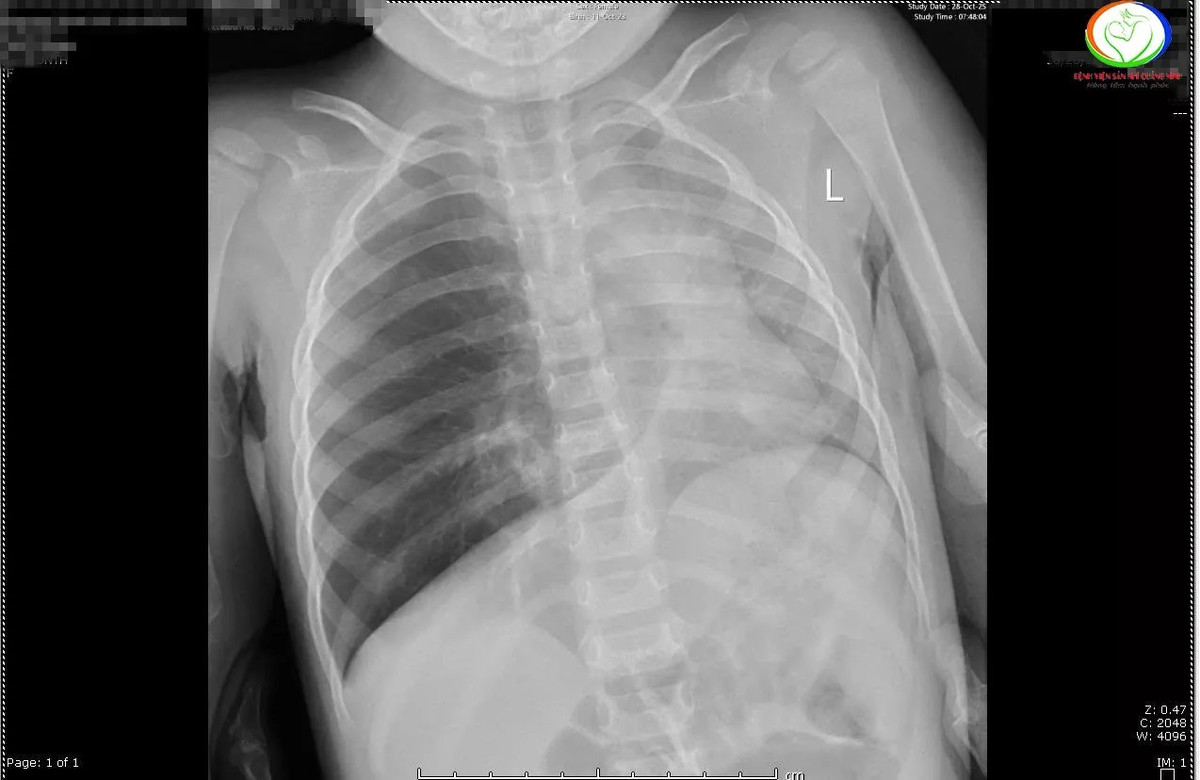

Qua phim chụp X –quang cho thấy các trẻ có hình ảnh ứ khí, mờ quanh rốn phổi. Riêng bệnh nhi N.N.L phổi trái giảm thể tích, kém sáng, xẹp phổi dạng dài thùy dưới phổi phải. Các bác sĩ đã hội chẩn khẩn cấp và chỉ định nội soi khí thanh phế quản cấp cứu gắp dị vật cho trẻ.

Kết quả nội soi ghi nhận tại phế quản gốc phải bệnh nhi N.N.L có dị vật hạt lạc kích thước 0,5×0,7cm, gây bít tắc hoàn toàn phế quản gốc phải.

Còn bệnh nhi Đ.M.A, dưới dây thanh khoảng 3cm phát hiện có dị vật mắc trong khí quản là mảnh xương cá kích thước 1,5x1cm gây xung huyết niêm mạc, xuất hiện dịch, phù nề thanh quản.